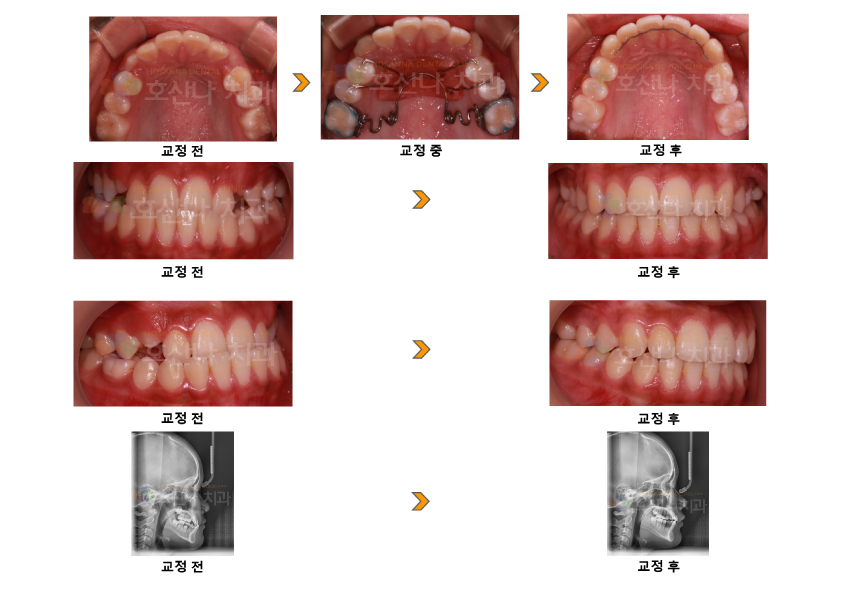

교정주걱턱 펜듈럼교정 시술 증례

< 주걱턱 펜듈럼교정 시술 증례 >

1. 치료대상

10y 11m  female

2. 교정치료이유

반대교합, 윗니의 송곳니 나올 자리가 없어요

3. 진단결과

1) Skeletal CL III

2) ant. Cross bite, U ant moderate crowding

4. Dr.Koo Memo

초진시 상,하 전치 반대교합으로 주걱턱의 소견을 보였는데 상악전방부의 공간 부족으로 #13,23 송곳니의 공간이 부족한 상태였습니다.

FACEC MASK로 상악턱의 이동은 완료 하였으나 구치부의 후방이동이 필요하지만 발치시 너무 들어가는 안모이므로

발치 하지 않고 펜듈럼을 통해 구치부의 후방이동을  시켜 완료 하였습니다.

5.교정기간

1y 9m